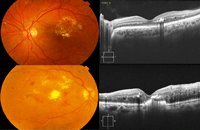

El desprendimiento neuroepitelial (DNE) puede presentarse aislado o acompañado de engrosamiento macular (

Figura 3). Es el estadio más grave y representa la evolución final de un edema macular crónico con rotura de las paredes de los quistes y acúmulo de fluido subfoveal. Murakami

Figura 3. Edema macular diabético con componente espongiforme, quístico y desprendimiento seroso del neuroepitelio.